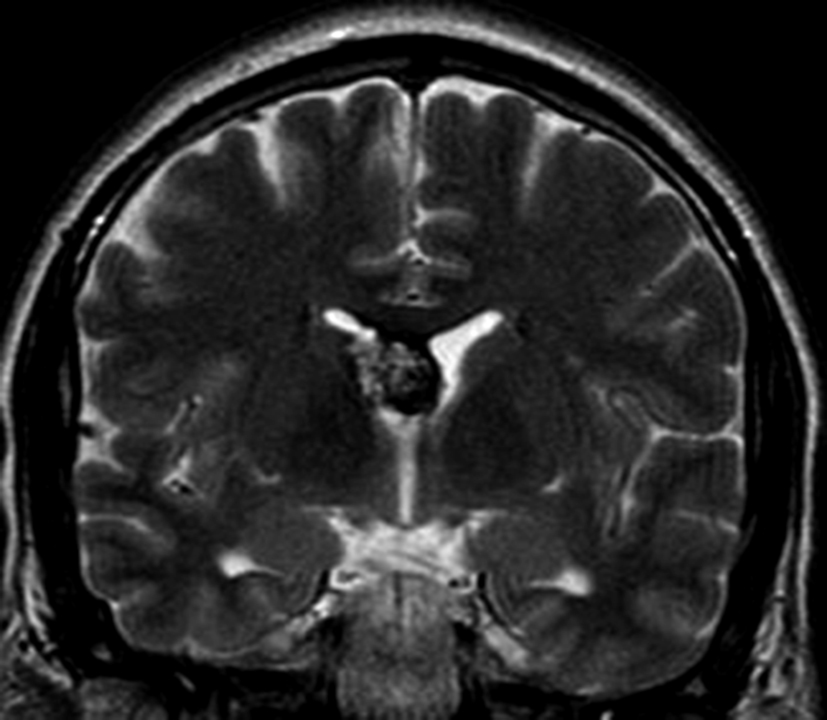

Figura 4

a y b) Imágenes coronales T2, Ay B. se evidencia la lesión con epicentro en el asta frontal del ventrículo lateral derecho y la extensión al cuero calloso.